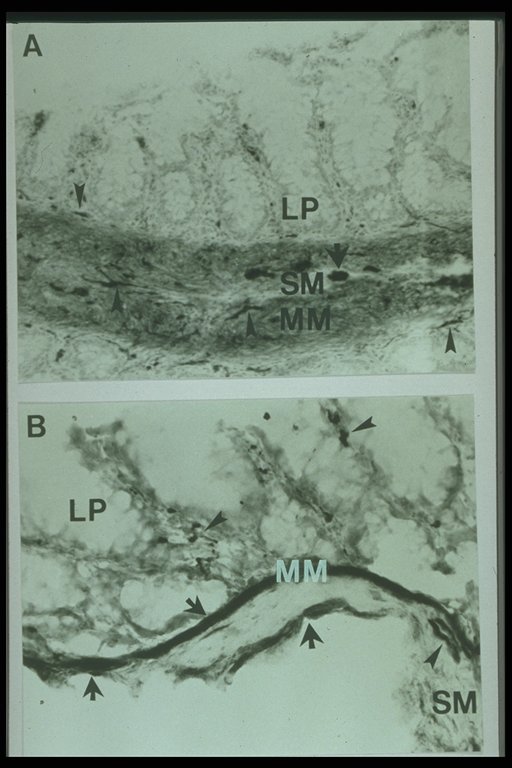

Increased acetylcholinesterase activity in Hirschsprung's disease, thick staining is observed in mucosa and submucosa layer (LP: lamina propria, MM: muscularis mucosae, SM: submucosa)